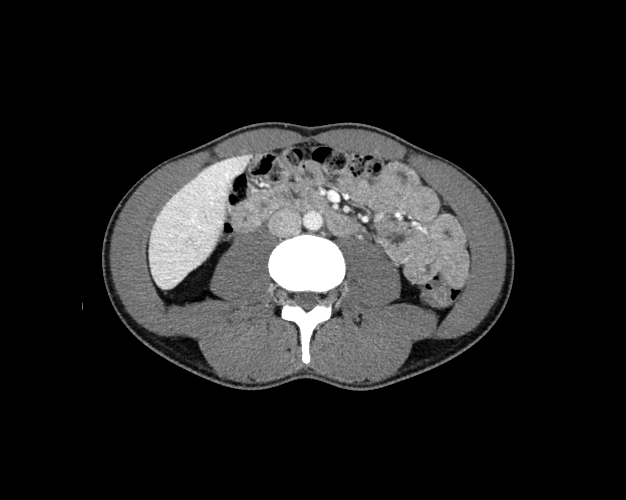

Body

Covers abdominal CT anatomy.